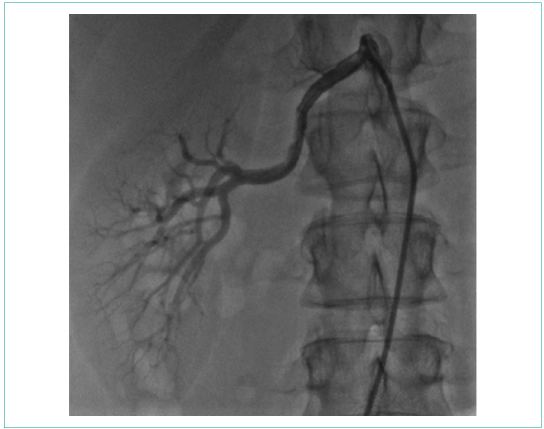

Рисунок 3. Ангиография правой почечной артерии (без гемодинамически значимых стенозов)

Picture 3. Right renal artery angiography (no hemodynamically significant stenosis)